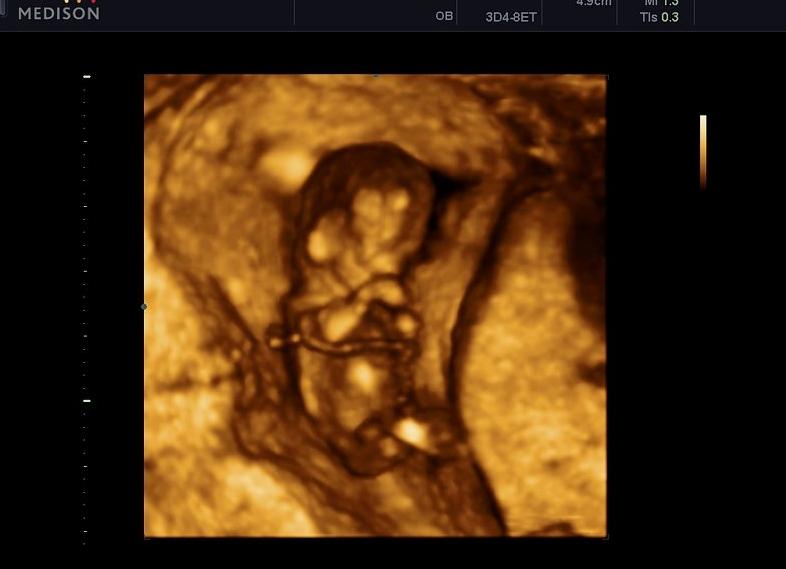

УЗИ на 12 неделе беременности

Именно после окончания первого триместра врач отправляет будущую маму на первое и самое важное ультразвуковое исследование. На нем устанавливается размер плода, динамика его развития и приблизительный срок родов. Важно УЗИ на 12 неделе беременности и для определения положения плаценты, состояния матки и отсутствия ее тонуса. Оценивается и количество околоплодных вод. К этому времени уже сформированы половые органы малыша, поэтому врач может определить пол ребенка на 12 неделе беременности. Но точного ответа еще может и не быть.

Еще одно важное исследование в конце первого триместра – это скрининг. Он представляет собой комплекс процедур, состоящий из УЗИ и биохимического анализа крови. Благодаря ему оценивается соответствие норме в протекании беременности и развитии малыша. Называют его еще двойным тестом.

УЗИ на 12 неделе беременности дает возможность изучить так называемую «воротничковую зону», расположенную в районе шеи между кожей и мягкими тканями ребенка. В этом месте скапливается жидкость, врач измеряет толщину данного пространства. Исследование помогает на раннем сроке выявить грубые пороки в развитии будущего ребенка (например, синдром Дауна), а также несовместимые с жизнью аномалии. Толщина воротничкового пространства на 12 неделе беременности не должна превышать 2,5 мм.

Воротничковая зона исчезает вместе с ростом малыша, поэтому важно проводить первый скрининг в отрезке между 11 и 13 неделями беременности.

Фото УЗИ на 12 неделе беременности